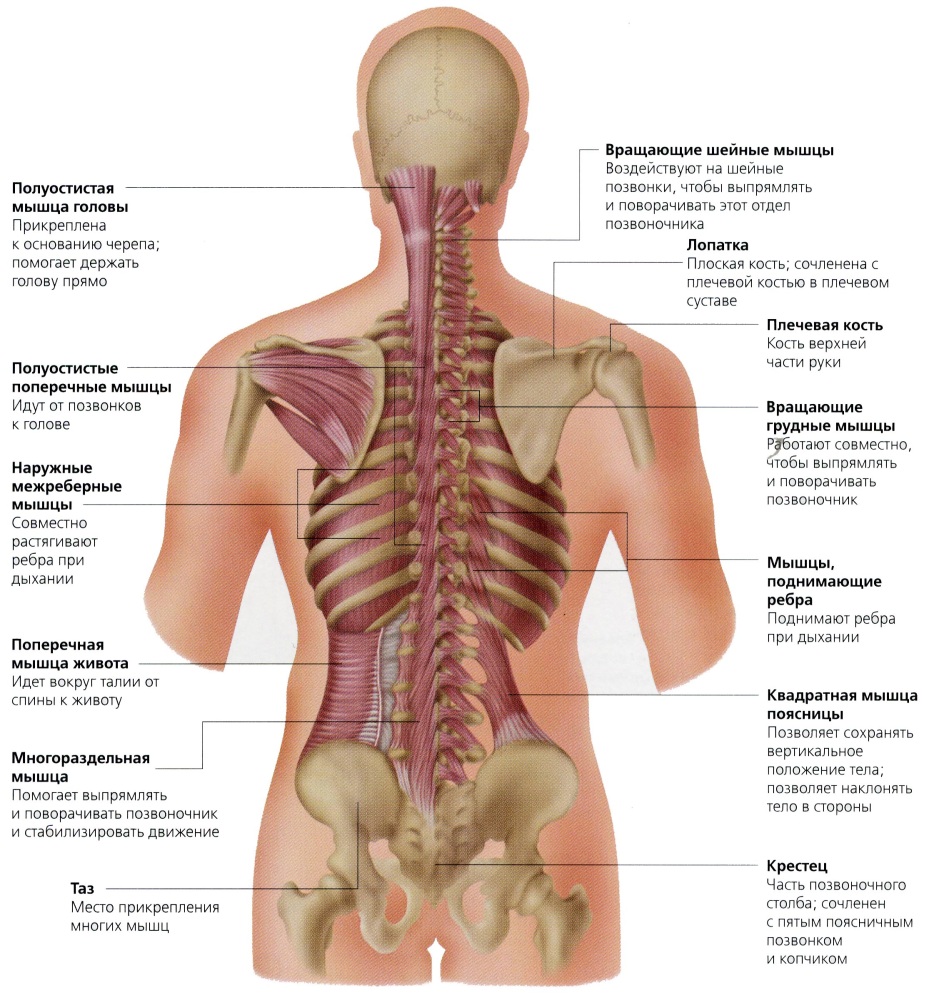

Изображения и визуализация внутренних органов человека